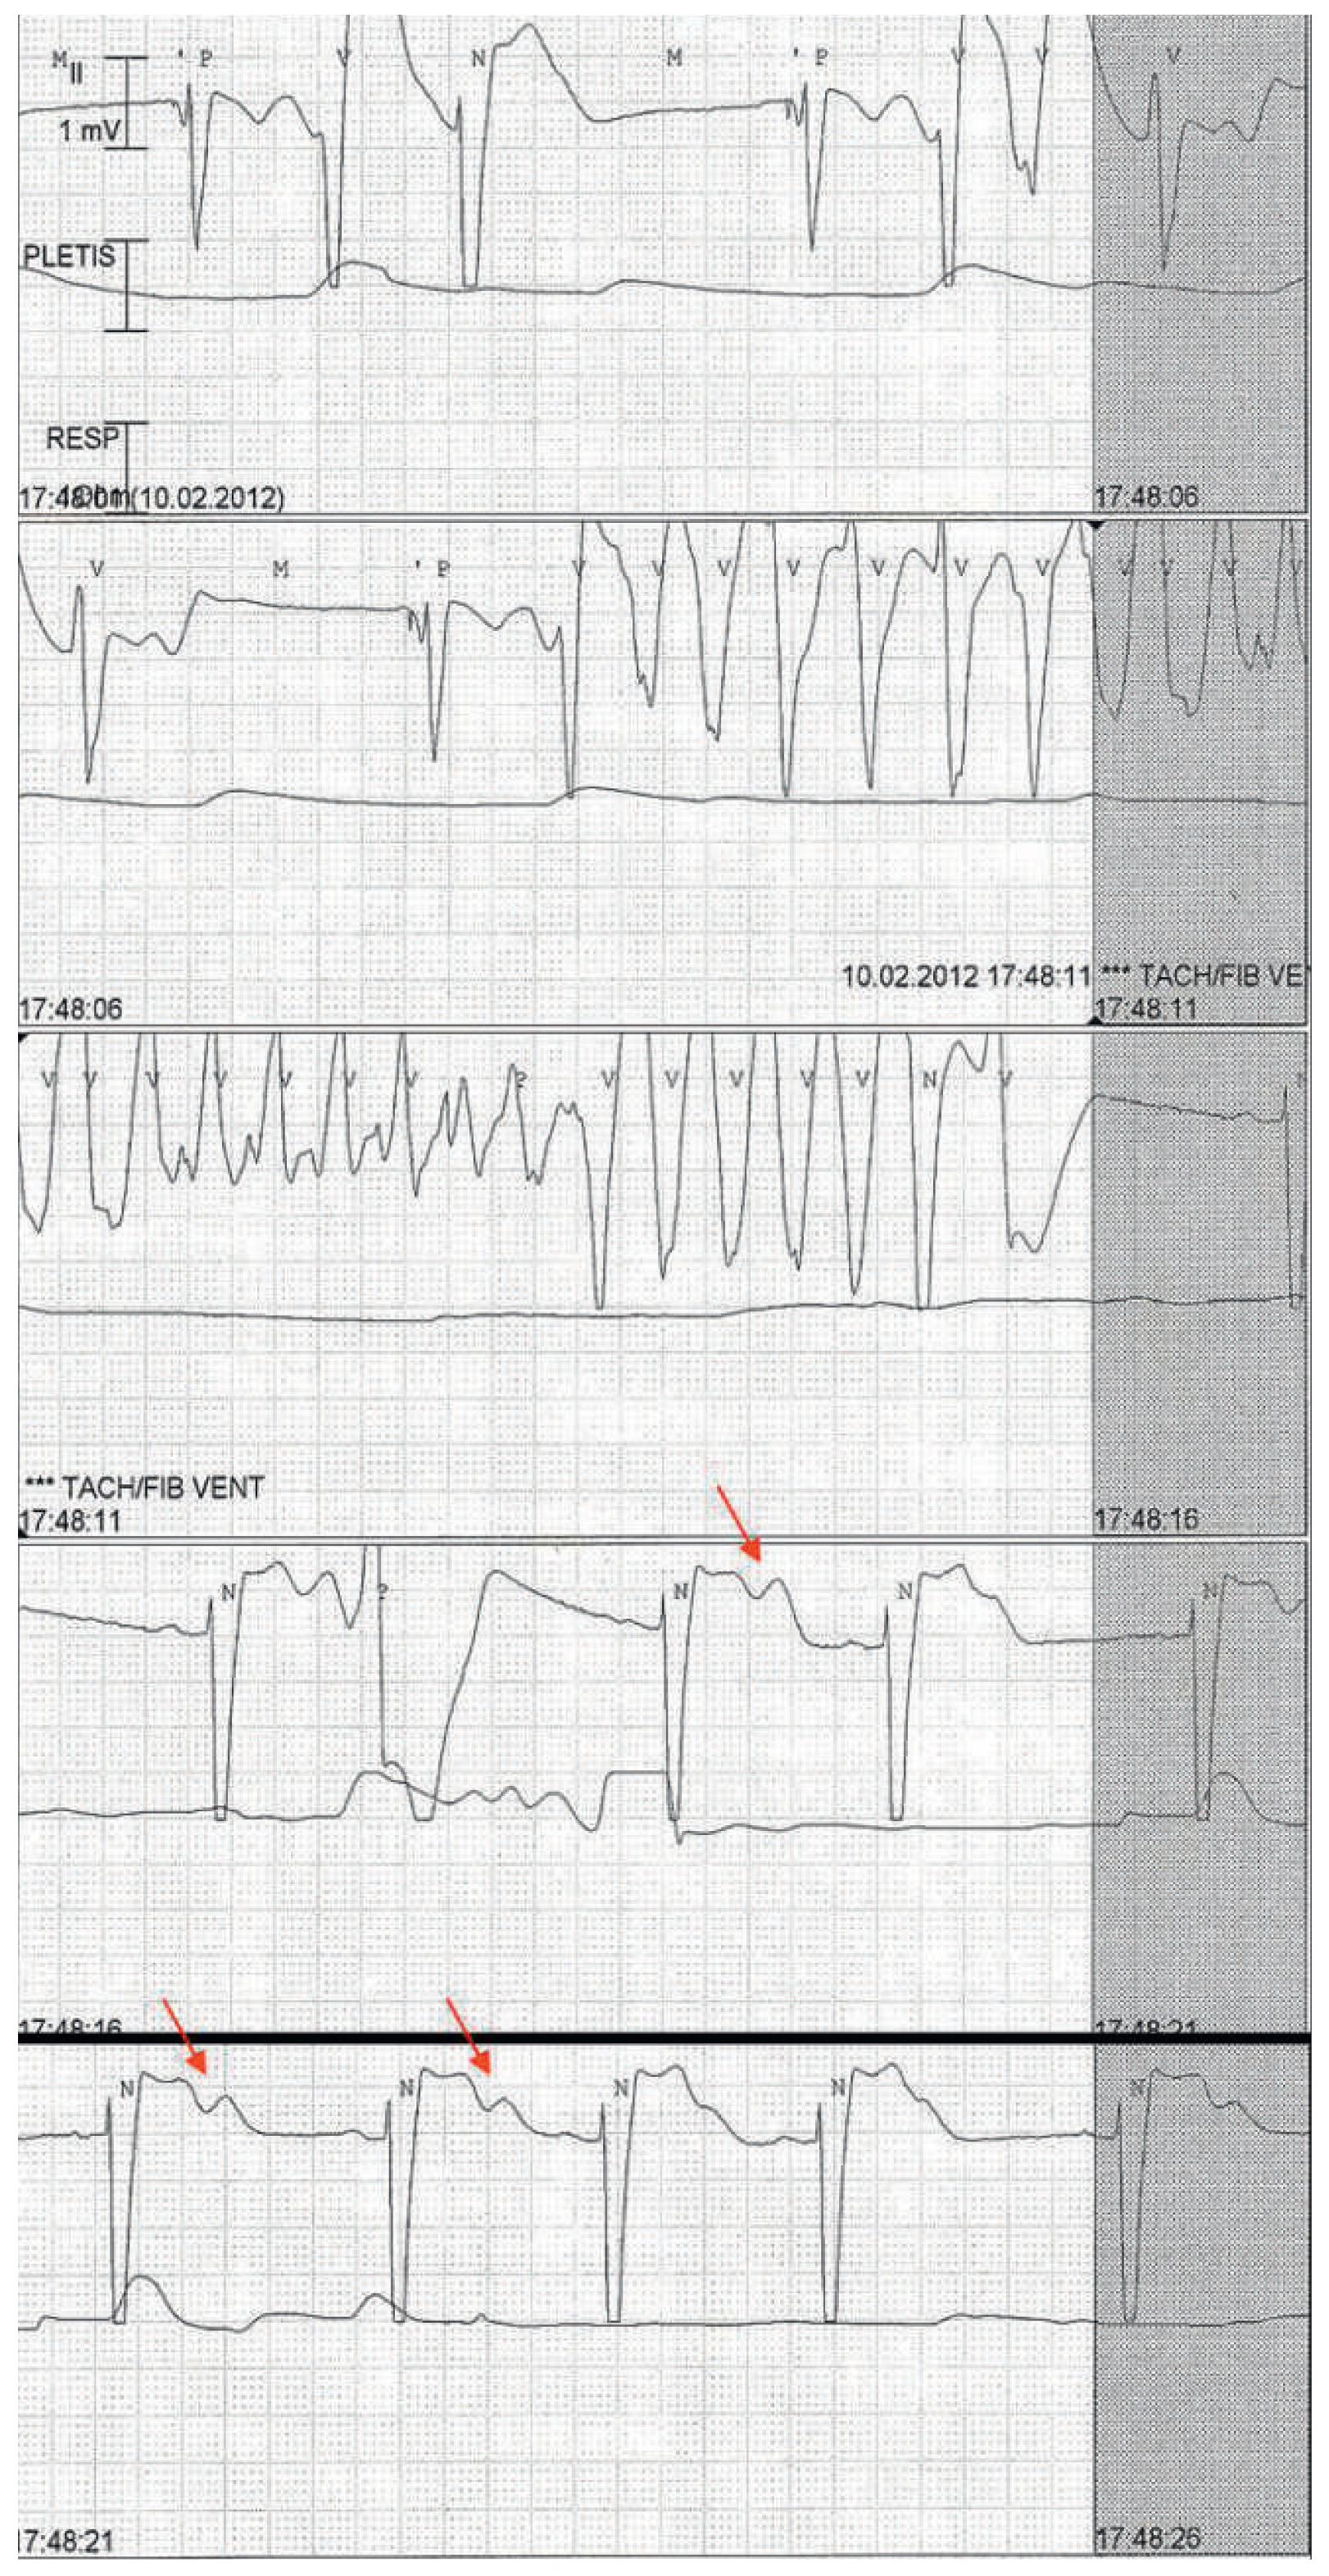

Shortly after admission the patient again had a pre-syncope. The ECG strip (fig. 2) documented an episode of self-terminated torsade de pointes preceded by a long interval (1580 msec) ended with a paced beat (VVI 40 bpm). The serum potassium concentration was 3.3 mmol/l (3.5–5.0 mmol/l), the mag- nesium 0.60 mmol/l (0.65–1.05 mmol/l).

Figure 2. ECG strip showing an episode of pause-dependent self-terminated torsade de pointes. The torsade is preceded by a pause (1580 ms) and a paced beat (VVI 40). Note also in the last 2 lines the pause-dependent notched T-waves (arrows) and a ventricular premature beat arising from the second component of the T-wave.

This case illustrates an example of acquired long QT syndrome complicated by torsade de pointes. Long QT interval was caused by a combination of electrolyte abnormalities (hypokalaemia and hypomagnesaemia), drugs (haloperidol and amiodarone), underlying decompensated heart failure and pauses due to relative bradycardia with premature atrial beats. As illustrated in figure 1, the T-waves are very abnormal with two components (notched T-waves, arrows). The second component represents early after-depolarisation that can lead to ventricular ectopic beats and can degenerate into torsade de pointes, the polymorphic ventricular tachycardia typically associated with long QT syndrome [1]. Tor sade de pointes is usually self-terminated leading to syncope, as in our case, but may degenerate into fatal ventricular fibrillation. In acquired long QT syndrome, torsade is typically pause-dependent, as a long cycle increases early after-depolarisation (increasing the notched T-wave) creating the basis for ventricular arrhythmia as depicted in figure 2 (arrows) [1]. It is, therefore, important to avoid long cycles, which was achieved in our case increasing the rate of the pacemaker.